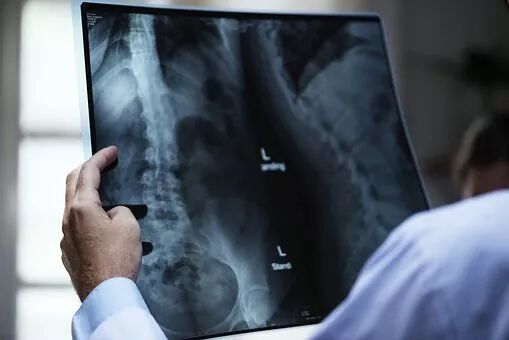

First, there is the fairly common greenstick fracture. This occurs when trauma to one side of the bone causes the other side of the bone to crack. The severity of a greenstick fracture can be very light – hard to see with the naked eye – or very severe, like the one in the image below.

What can parents do if they’re worried about exposing their child to radiation during X-rays?

There is no need to worry about this. First of all, nowadays we use digital X-rays, which give off very little radiation. According to the most recent medical reports, moderate and necessary radiation contact won’t be harmful to your child. The effects are so mild that even pregnant women can get them. Furthermore, doctors take special precautions to protect children’s fragile areas, like their thyroids and perianal regions. Finally, doctors will only order X-rays if they’re absolutely necessary. In general, depending on the severity of the injury, your child may have to get up to four X-rays.

Because children naturally are very active, they may still be able to move an injured area as long as the pain is lightly relieved – and this can cause their cast to become displaced. That’s why your doctor may order an X-ray in the early stages of your child’s recovery. In my experience, around 20% of fracture cases need to be retreated, as the injury may have been disrupted by the cast being displaced. This can happen even as soon as the day after the cast is set.